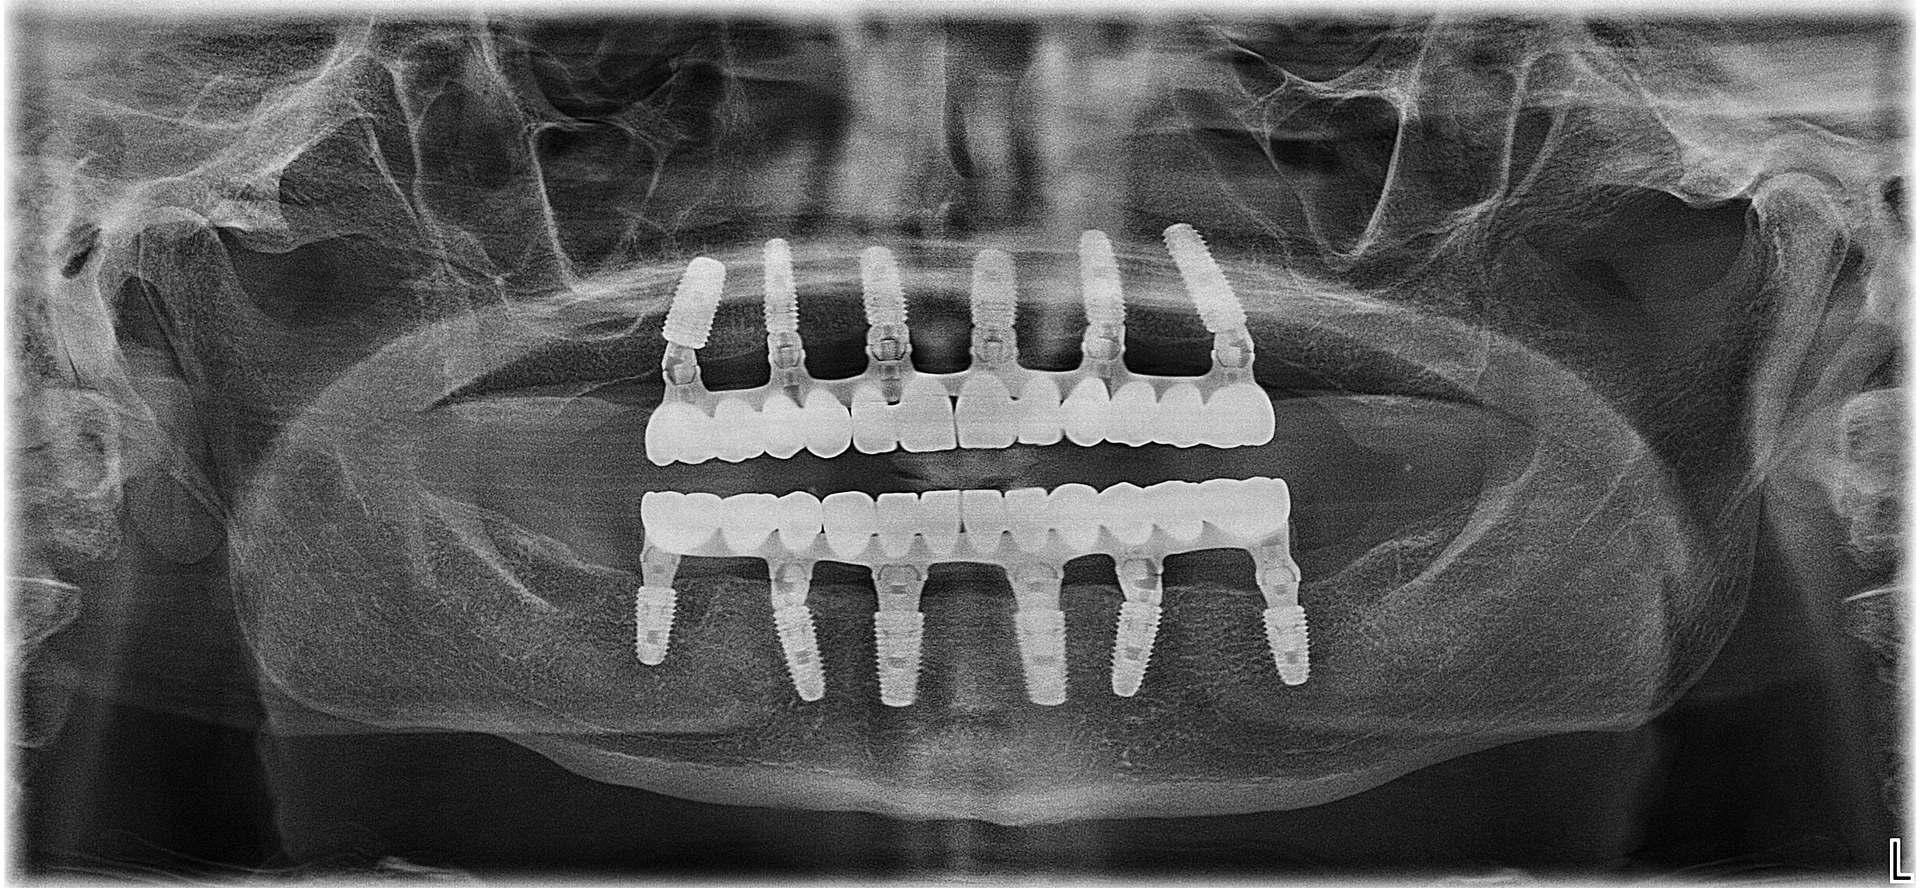

Sistemul Dantură pe implanturi dentare implică un număr redus, dar totuși extrem de eficient de implanturi dentare, care inserate în poziții cheie conferă siguranța de care ai nevoie / siguranța unei danturi sănătoase. Mai mult decât atât, această intervenție este minim invazivă, iar recuperarea este mult mai ușoară.